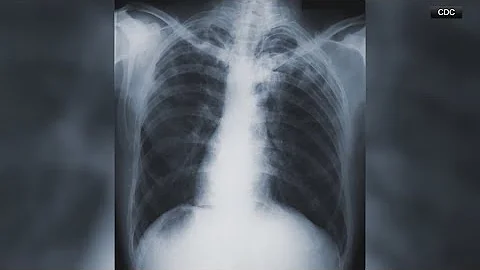

Largest U.s. Tuberculosis Outbreak In Kansas Since 1950 Reported - Dr. Vin Gupta

Health officials report the largest U.S. tuberculosis outbreak in Kansas since 1950, with 67 symptomatic and 79 latent cases; ...